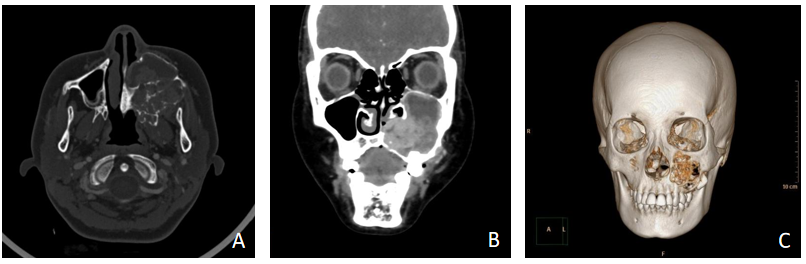

《上颌骨中心性透明细胞型黏液表皮样癌1例》为13岁女性患者,因“左侧面部肿胀2月”入院。影像学提示该病例为左侧上颌窦及上牙槽区病变,多考虑恶性,造釉细胞癌可能性大。术前在口腔医院病理科行细针穿刺检查,镜下见少量细胞团,细胞体积稍大,胞浆淡染,诊断为(左上颌骨)不排除肿瘤可能。术后结合HE形态及免疫组化染色、特殊染色,诊断为(左上颌骨)透明细胞型黏液表皮样癌。

图 1 影像资料